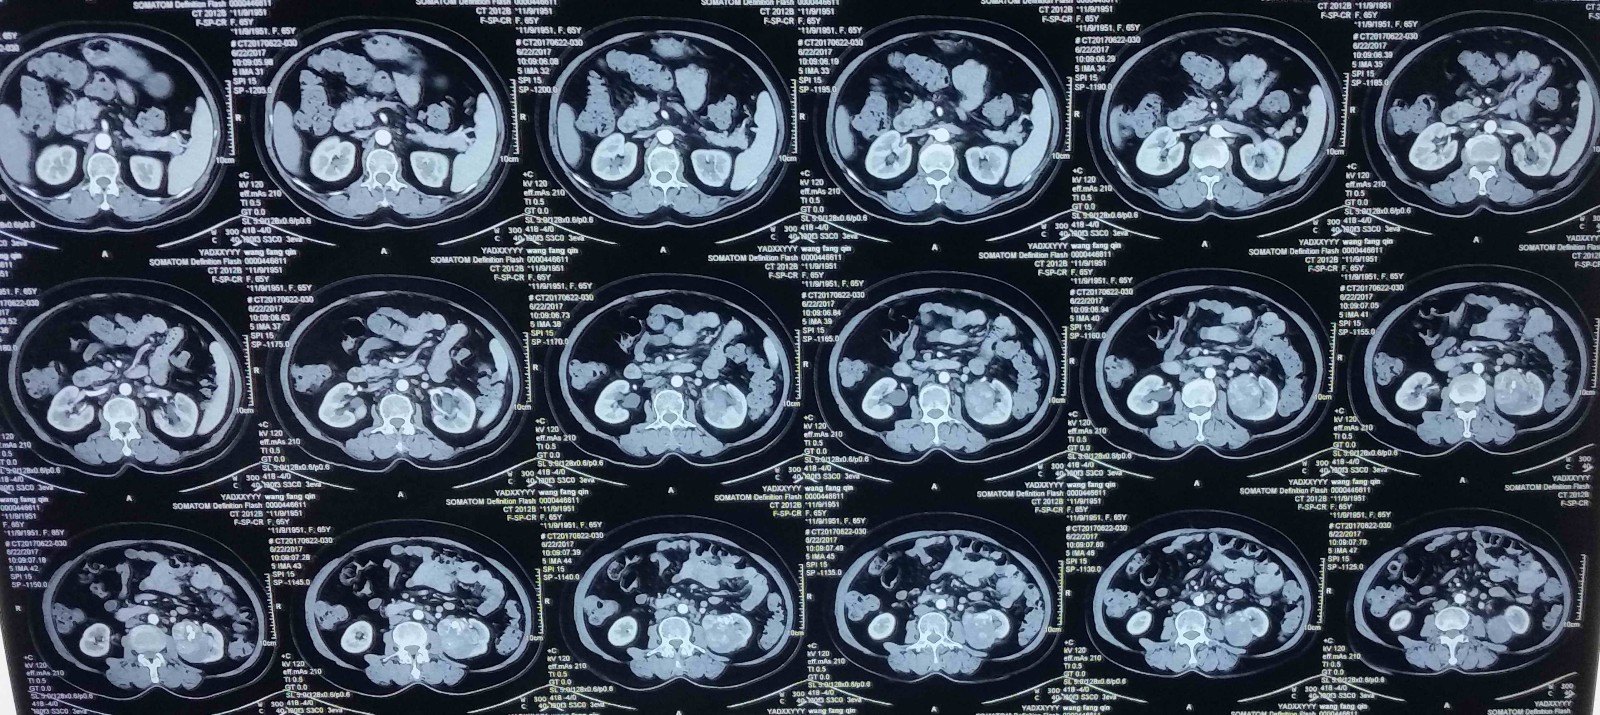

男性,45岁。B超发现左肾肿物2个月。考虑为肾